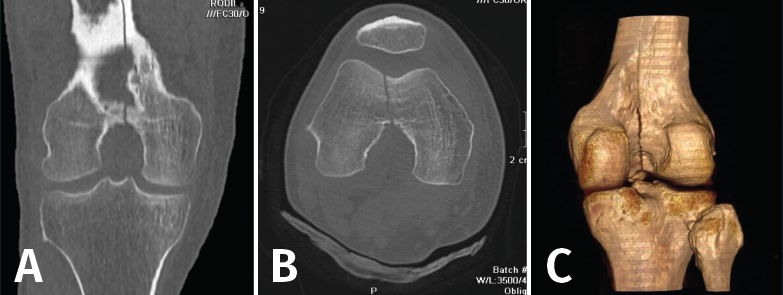

1. Fracturas

Es esencialmente útil en la valoración de los trazos de fractura, de su extensión, del escalón intraarticular y el desplazamiento. También es importante en la planificación del tratamiento de las fracturas intraarticulares complejas.

Los nuevos equipos, con múltiples detectores, permiten realizar cortes finos (submilimétricos) y reconstrucciones en cualquier plano del espacio o tridimensionales (3D) de gran calidad, que facilitan la valoración de estas lesiones(7).

1.1. Fémur (Figuras 18 y 19)

Figura 18. A: corte de reconstrucción coronal; B: axial; y C: reconstrucción 3D de tomografía axial computarizada de rodilla: fractura longitudinal del fémur extendida al techo intercondilar.